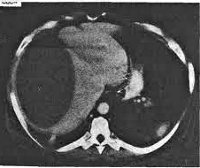

Главное значение в диагностике поддиафрагмального абсцесса отводится рентгенографии и рентгеноскопии грудной клетки. Для поддиафрагмального абсцесса характерно изменение в области ножек диафрагмы, более высокое стояние купола диафрагмы на пораженной стороне и ограничение ее подвижности (от минимальной пассивной подвижности до полной неподвижности). Скопление гноя при безгазовых поддиафрагмальных абсцессах видно как затемнение над линией диафрагмы, наличие газа – как полоса просветления с нижним горизонтальным уровнем между абсцессом и диафрагмой. Определяется выпот в плевральной полости (реактивный плеврит), снижение воздушности нижних частей легкого.

МСКТ и УЗИ брюшной полости позволяют подтвердить наличие жидкости, гноя и газа в брюшной или плевральной полости, изменение положения и состояния прилежащих внутренних органов (например, деформацию желудка, смещение продольной оси сердца и др.). Диагностическая пункция абсцесса допустима лишь во время операции.